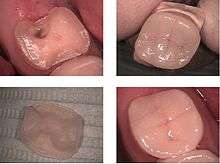

Another consideration is unsupported tooth structure. In the photo at right, unsupported enamel can be seen where the underlying dentin was removed because of infiltrative decay. When preparing the tooth to receive a restoration, unsupported enamel is removed to allow for a more predictable restoration. While enamel is the hardest substance in the human body, it is particularly brittle, and unsupported enamel fractures easily.

In this technique the restoration is fabricated outside of the mouth using the dental impressions of the prepared tooth. Common indirect restorations include inlays and onlays, crowns, bridges, and veneers. Usually a dental technician fabricates the indirect restoration from records the dentist has provided of the prepared tooth. The finished restoration is usually bonded permanently with a dental cement. It is often done in two separate visits to the dentist. Common indirect restorations are done using gold or ceramics.

While the indirect restoration is being prepared, a provisory/temporary restoration is sometimes used to cover the prepared part of the tooth, which can help maintain the surrounding dental tissues.